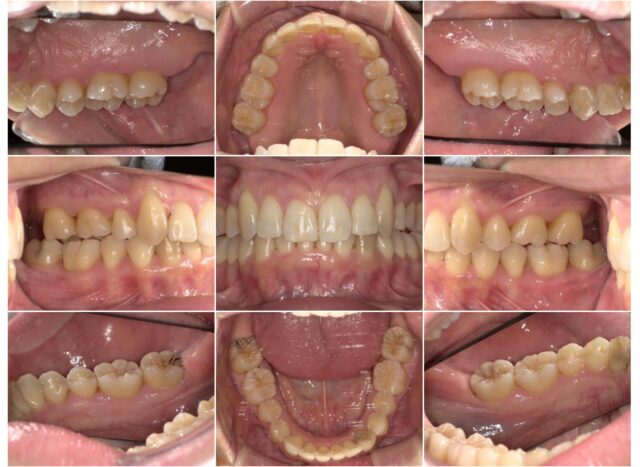

症例紹介

before

after